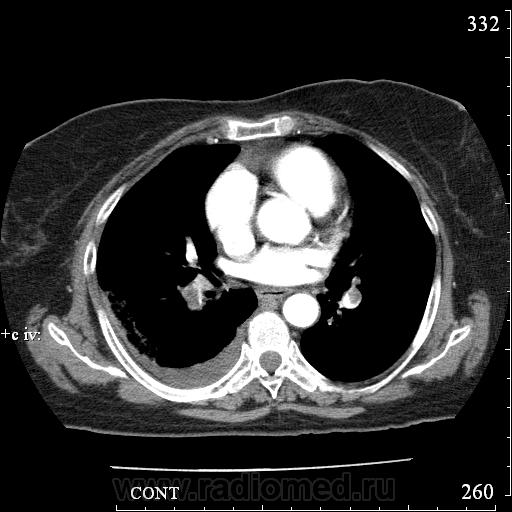

Еще один случай диагностики ТЭЛА методом КТ-ангиографии у женщины 59 лет. Основная клиническая жалоба - выраженная одышка. Определяется: полный дефект наполнения в системе правой ЛА (бифукация и нижнедолевая), неполный дефект наполнения в левой ЛА (нижнедолевая), пристеночные тромбы по задней стенке в области бифуркации обеих легочных артерий. Инфаркт (массивное кровоизлияние) нижней доли правого легкого. Правосторонний малый (120см3) гидроторакс. Несмотря на выраженные тромбы, поперечники легочных артерий - в пределах нормы.; на нативной (безконтрастной) КТ - тромбы не видны. Несмотря на почти полный дефект наполнения в левой нижнедолевой артерии, изменений в легочной ткани левого легкого нет. Также приводится топограмма, как вариант, приближенный к рутинной рентгенограмме